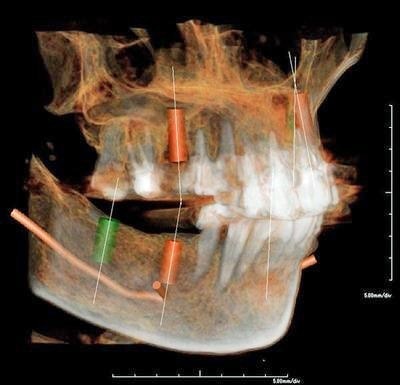

CTによる詳細な現状把握

レントゲンでは把握できないことまでCTでは確認することが出来ます。

身体を断面や立体図として見ることができ、骨はもちろんの事、神経や血管に至るまで確認することができます。

そのデータを元に、どのような角度、どのような深さでインプラントを打ち込むかなど、的確な治療計画を立てることができます。